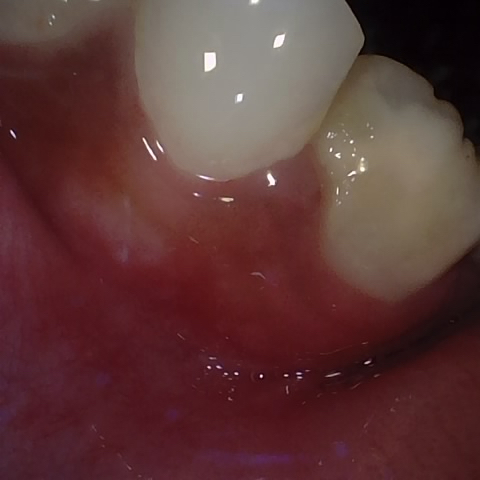

Incorrect Quality Level

The reference annotation for this image is

None

.

Please select the correct quality level.

Annotated as "Good"